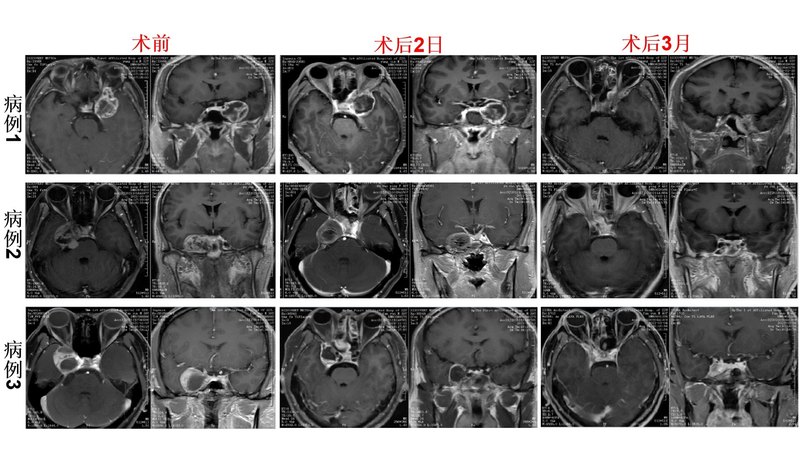

對于“海綿竇內(nèi)三叉神經(jīng)鞘瘤”,傳統(tǒng)方法多采用“巨大骨瓣開顱切除”的方式,術(shù)后大多遺有嚴重神經(jīng)功能障礙?!吧窠?jīng)內(nèi)鏡下經(jīng)鼻-翼突入路切除海綿竇病變”能夠?qū)崿F(xiàn)“不用開顱而切除顱內(nèi)病變”,該術(shù)式利用頸內(nèi)動脈與顱神經(jīng)之間的“神經(jīng)-血管間隙”操作,“不損傷神經(jīng)功能”,不影響腦組織而實現(xiàn)“閃電式出院”。最近,我們團隊完成3例“經(jīng)鼻-翼突入路海綿竇內(nèi)三叉神經(jīng)鞘瘤切除術(shù)”,3例,具體如下。手術(shù)治療后3月,可見術(shù)區(qū)填塞物基本吸收,手術(shù)通道區(qū)域愈合良好,局部未見明顯腫瘤復(fù)發(fā)跡象。所有患者復(fù)查均未見明顯顱神經(jīng)損傷癥狀。隨著病例積累,截至目前,我們已經(jīng)完成內(nèi)鏡經(jīng)鼻側(cè)顱底腫瘤切除術(shù)17例,均確定良好效果。相關(guān)結(jié)果,我們已經(jīng)形成科學(xué)論文,會近期發(fā)表。